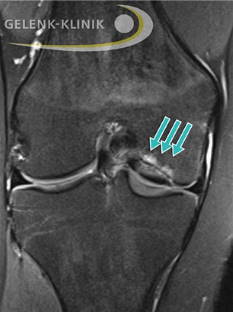

Die MRT-Aufnahme zeigt ein abgelöstes, aber im “Mausbett” befindliches Dissekat im Kniegelenk. © Gelenk-Klinik